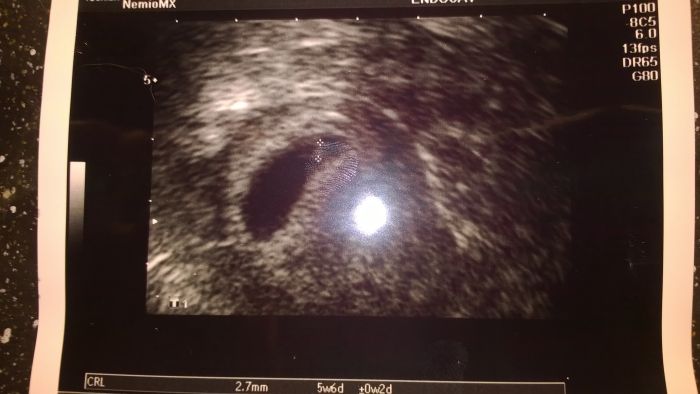

Ahojky,tjak jsme se právě vrátili. Náš mrňousek je mrňavý, opět ho nemohla paní doktorka najít, ale našla. A i když je tak malinký, tak odpovídá stáří. Včera byl o den napřed a dnes o den míň, ale to je to jejich měření. Beru to opravdu s rezervou. Podle dneška máme 2,7mm a podle včerejšku 3mm. Další kontrola za 14 dní v Pronatalu a zítra se budu objednávat ke svému dr. a doufám, že mě objedná na pondělí a vystaví mi neschopenku Srdíčko bije jak o závod